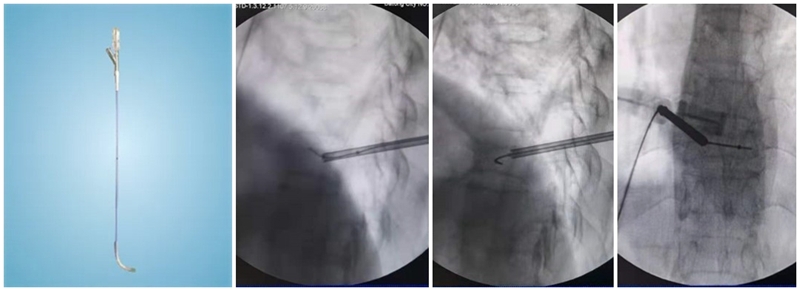

(4)置入球囊:插入带导丝弯角球囊时注意透视球囊方向,反复调整务必与终板平行。如需要拔出球囊调整方向,务必先拔导丝再拔球囊,透视球囊标记点必须完全从工作套管内出来,否则易造成弯角球囊与工作套管边缘卡磨破裂。

(5)扩张球囊:注入造影剂扩张球囊过程中,注意观察术中正侧位透视图像,控制压力值,不必苛求球囊顶到上下终板,以免发生医源性终板破裂,造成椎间隙骨水泥渗漏可能。注意弯角球囊扩张完毕后拔除顺序:先拔导丝再拔球囊。